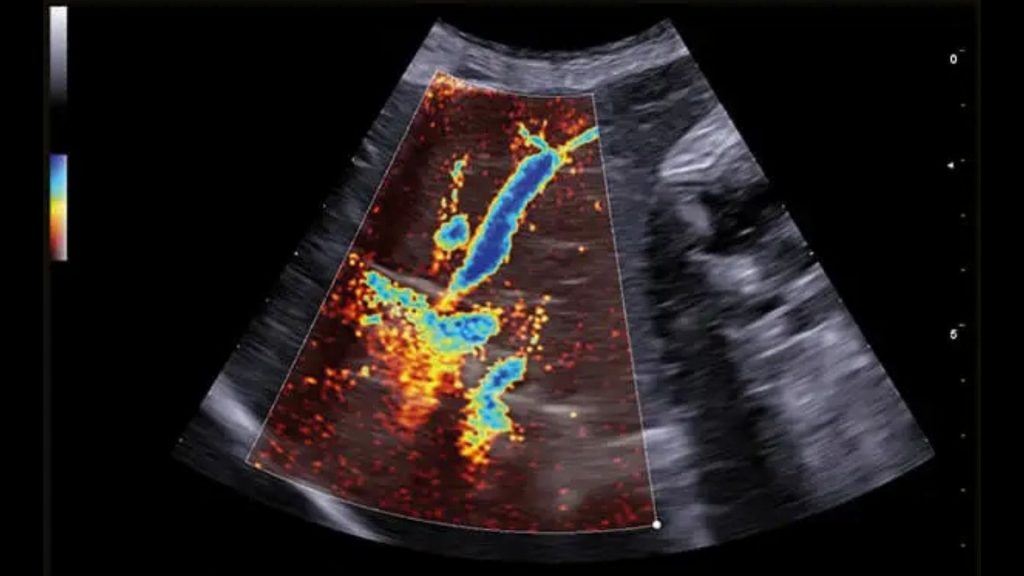

Karaciğer ultrasonografisinde, hepatik parankim (karaciğer dokusu), büyük hepatik ve portal damarlar, bitişiğinde caudal vena cava ve safra kesesi ve bilier sistem incelenir. Radyografiden farklı olarak ultrasonografi, hedef yapıların çeşitli düzlemlerden görüntülenmesine olanak sağlar. Karaciğerin ultrasonografik muayenesi sırasında hekimin tercihine göre hasta sağ yan, sol yan veya sırt üstü pozisyonlarında yatabilir. Daha iyi görüntü alınabilmesi için karın bölgesi göğüs bölgesine kadar tıraşlanıp temizlenmelidir. Görüntü kalitesini hastanın vücut yapısı, karaciğerin boyutu ve gastrointestinal içerik etkileyebilir. Mide içeriğindeki gaz iyi bir karaciğer görüntülemesinin önündeki en önemli engeldir. Bu sebeple hastanın aç olarak muayene getirilmesi tercih edilir. Karaciğer ultrasonografisine ihtiyaç duyulan durumlar, karaciğer hastalıklarıyla ilişkili klinik belirtiler (kusma, ishal, abdomende genişleme, abdomenin elle muayenesinde karaciğer boyutunun arttığının farkedilmesi vs.), laboratuvar analizlerinde biyokimyasal değişiklikler (ALT, ALP, AST, NH3, GGT, BİLİRUBİN, TOTAL PROTEİN, ALBUMIN), ikterus (sarılık), hepatomegali, asites, akut abdomen veya abdominal kitle şüphesi, metastatik kitle şüphesi, hepatik enseflaopati, immun sistem hastalıklarını içermektedir. Hepatik arterleri ve intrahepatik dallarını görüntülemek için Doppler muayenesi gereklidir. Doppler ultrasonografi ile hepatik arter, portal ven ve caudal vena cava incelenebilir. Konjenital veya edinsel Portasistemik Şantla (PSŞ) ilişkili klinik veya laboratuvar belirtileri olan hayvanlarda intrahepatik veya ekstrahepatik anormal damarlar da saptanabilir. Doppler görüntüleme ile aynı zamanda intrahepatik portal hipertansiyonun da tanısı konulabilmektedir.

Veteriner hekimlerimize ve sevimli dostlarımıza merkezimiz bünyesinde vermiş olduğumuz Veteriner USG hizmetimizde Esaote MyLAB X8VET Üst Düzey Renkli Doppler Ultrasonografi Cihazı ile hizmet vermekteyiz. Cihaz ile yapılan sonografik ve doppler çalışmalarında her türlü patolojilerde yüksek çözünürlükte görüntüleme imkanı sağlanmaktadır. İçerdiği yazılımlar ile tanıyı detaylandırarak teşhise götüren götürmeye yardımcı olmaktadır. Çoklu modalite aracı ile, hızlı bir tanıya ulaşmak için gerçek zamanlı ultrason görüntülemeyi çok çeşitli ikinci görüntüleme modaliteleriyle (MRI, CT, 3D Görüntüleme, Doppler) birleştirmek mümkündür.